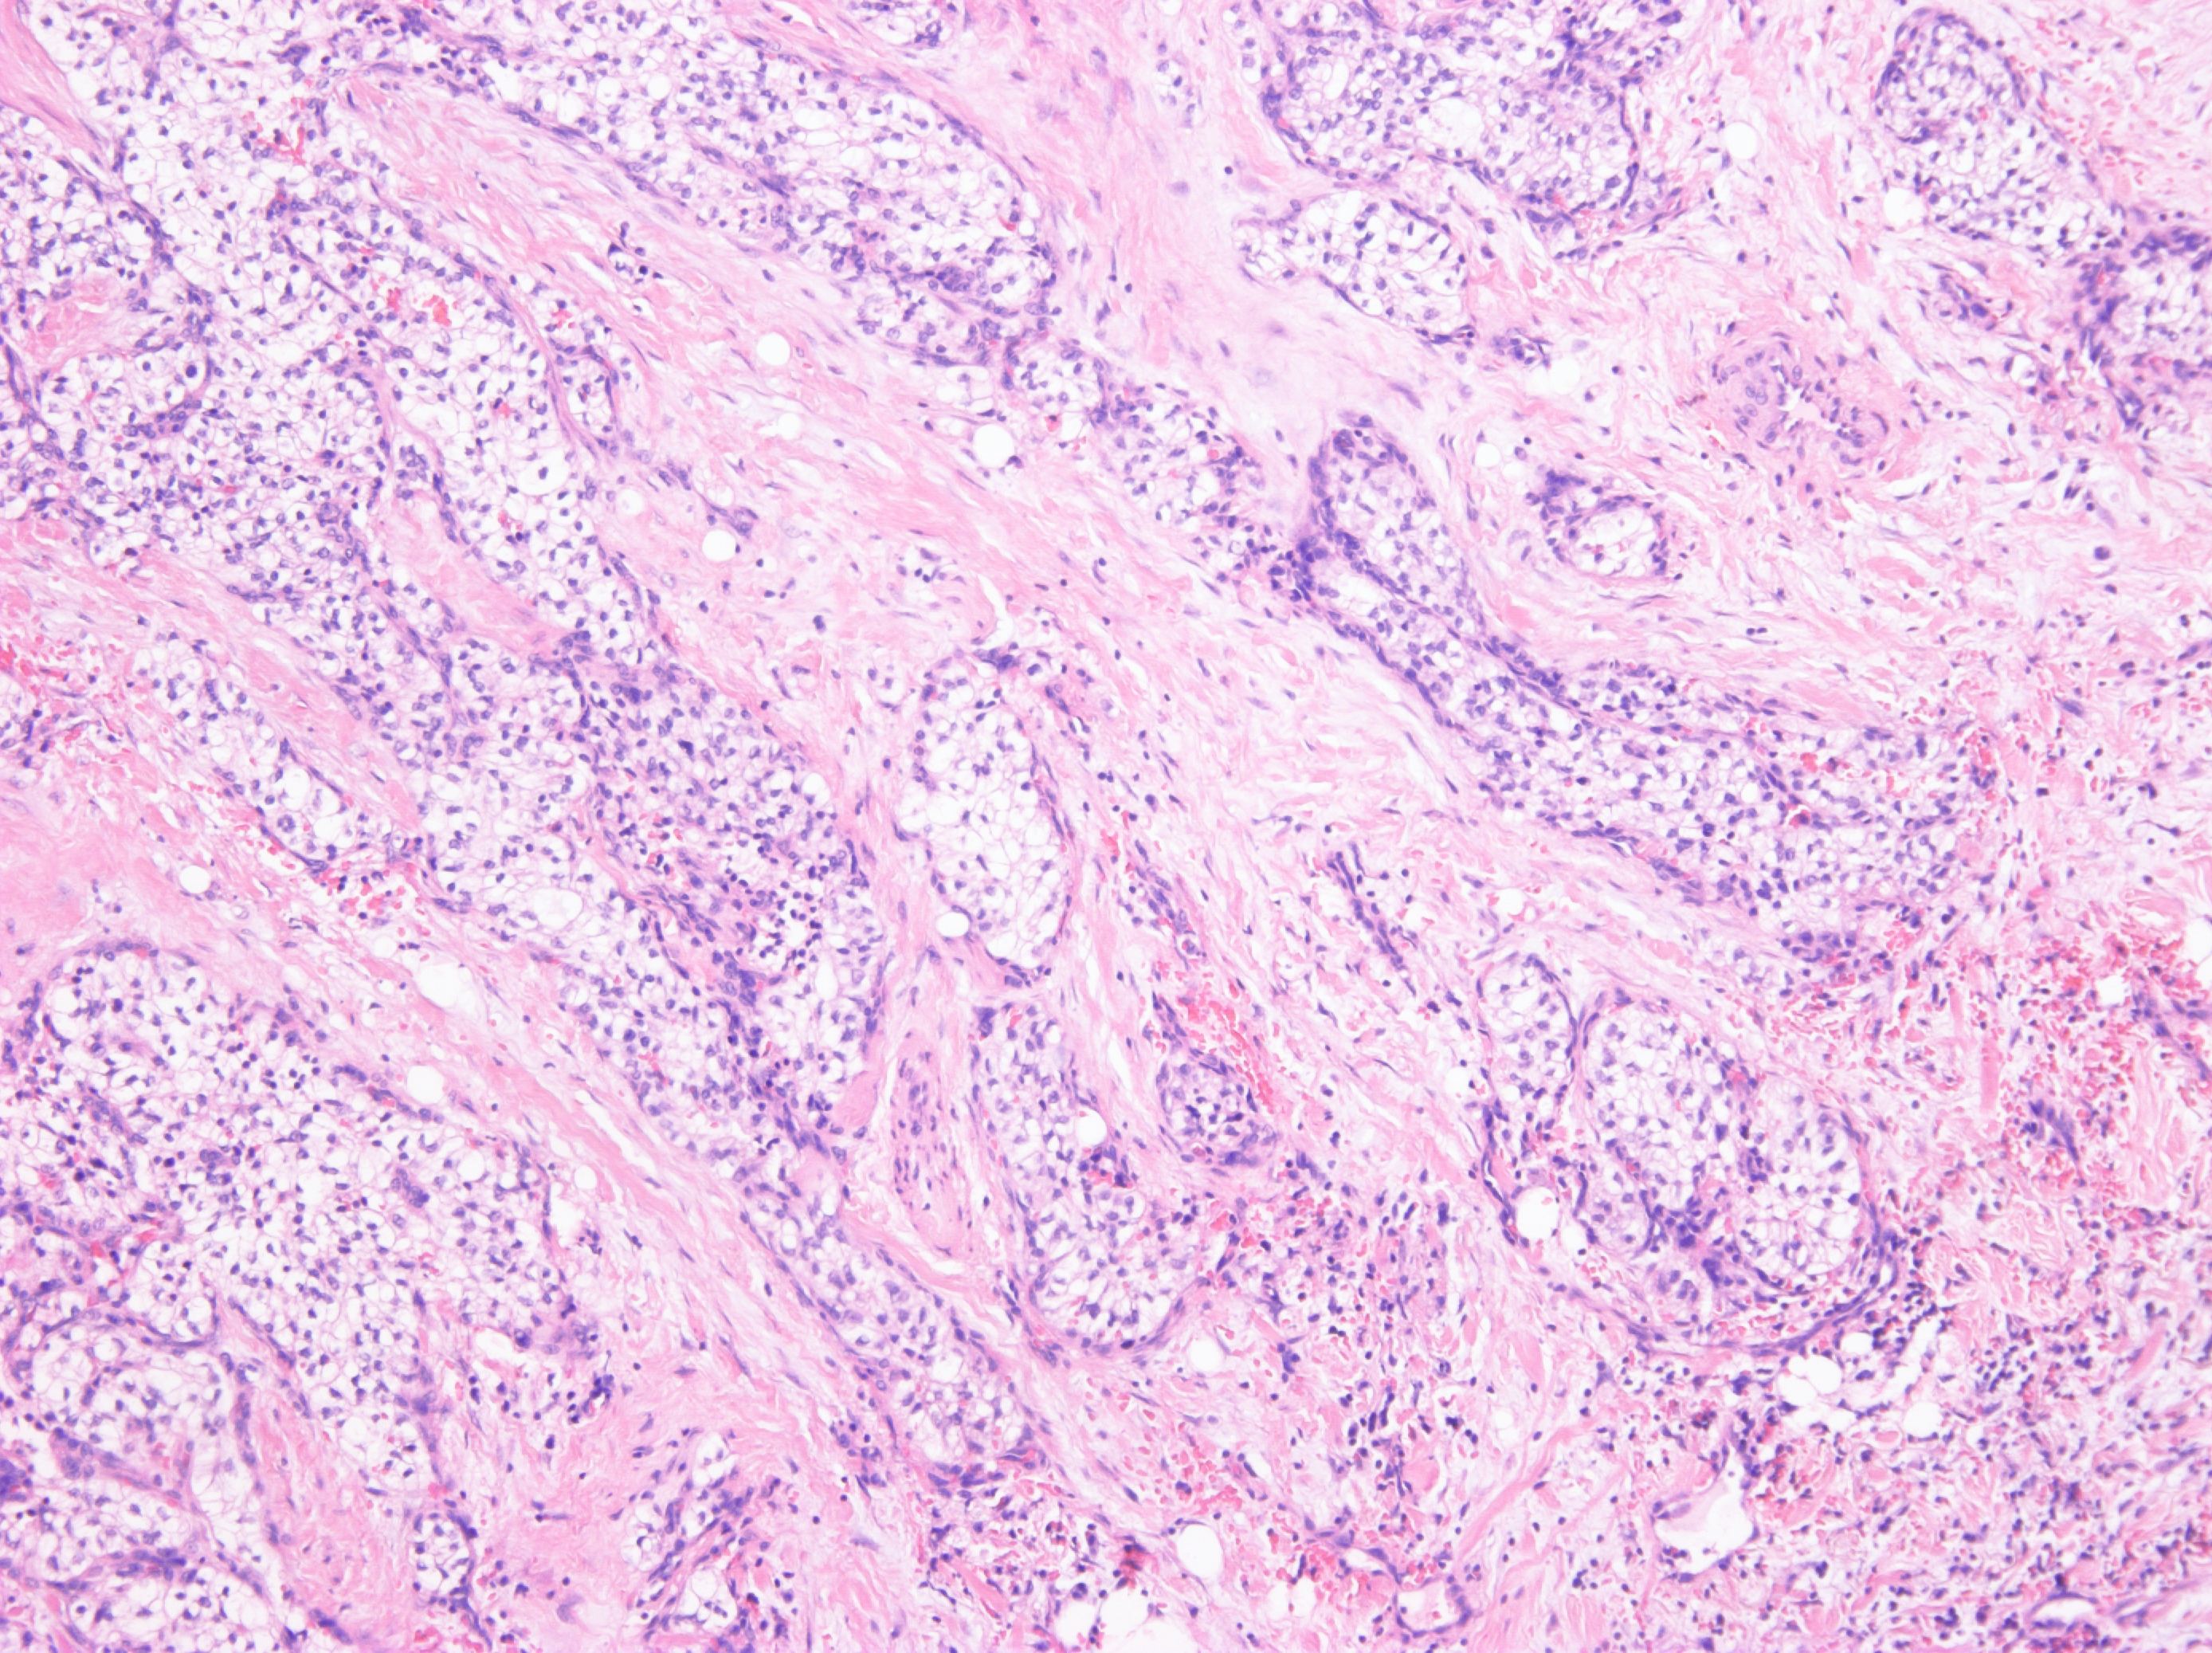

Consensus grade: Renal cell carcinoma with leiomyomatous stroma

Since there is a lot of pink stroma, this is probably thought to be clear cell renal cell carcinoma with leiomyomatous stroma but the photos show a stroma which looks fibrous to me so garden variety clear cell renal cell carcinoma is a better diagnosis for the photos. |

hard to be sure the stroma is muscle in these images |

Kidney tumor, male 62-year-old. Tumor well circumscribed, yellow color with gray strands on gross section. Tumor composed of clear cell elements resembling cells of typical clear cell RCC. Fibroleiomyomatous stroma was prominent. No sarcomatoid changes were present.

Tumor is positive for CK 7, vimentin. Using next generation sequencing, no abnormalities of VHL gene (methylation, mutation, LOH3p) and TCEB1 gene were disclosed.

Dg: Renal cell carcinoma with (fibro)leiomyomatous stroma